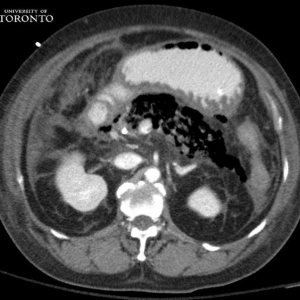

病例学习:胰腺炎影像诊断技巧

病史:女性,73岁,既往有原发性高血压和Ⅱ型糖尿病,因发热和腹部剧痛来急诊室就诊。该患者在急诊室观察时休克昏厥。该患者被送入重症监护室,并给予高剂量抗生素静脉滴注。之后患者病情稳定,未进行手术治疗。两个 ...